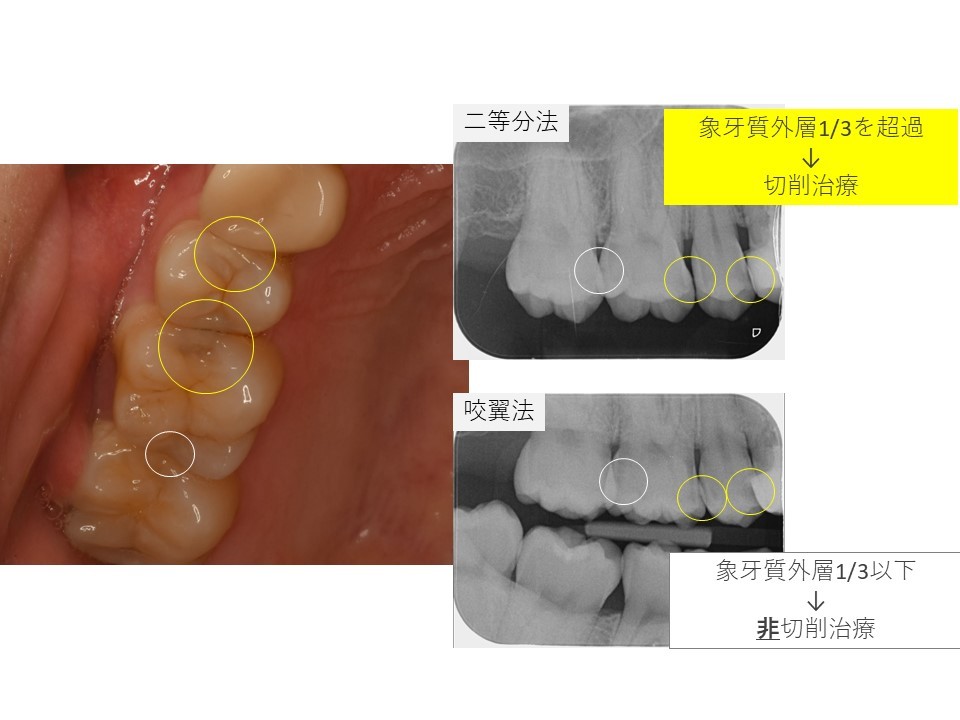

黄色の〇の場所にむし歯があります。

レントゲンを撮影します。

当院ではデンタル14枚法に加えて、咬翼法も併用して、

読影の精度を高めて、治療方法の根拠をお示ししています。

黄色〇のほかに、白い〇のところにもう蝕が確認されました。

こちらは現時点で基準以下の大きさと判断して、非切削治療を選択しました。